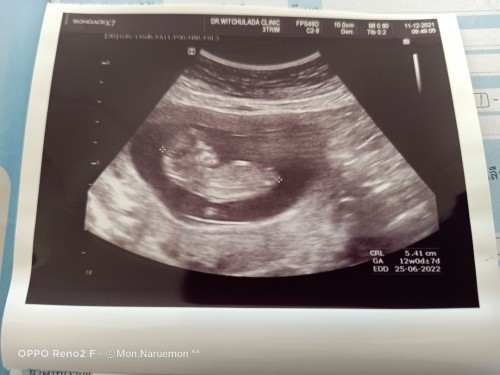

ไปหาหมอเมื่อวันที่ 11 ธ.ค. 64 ตื่นเต้นมากๆ สรุปลูกน้ำหนักตามเกณฑ์ เสียงหัวใจดี น้องดิ้นดีมากเลยค่ะ ชื่นใจไปอีกค่ะจากที่เคยกังวล😅 ขอบคุณแม่ๆทุกบ้านนะคะ ที่มาเป็นกำลังใจให้ค่ะ